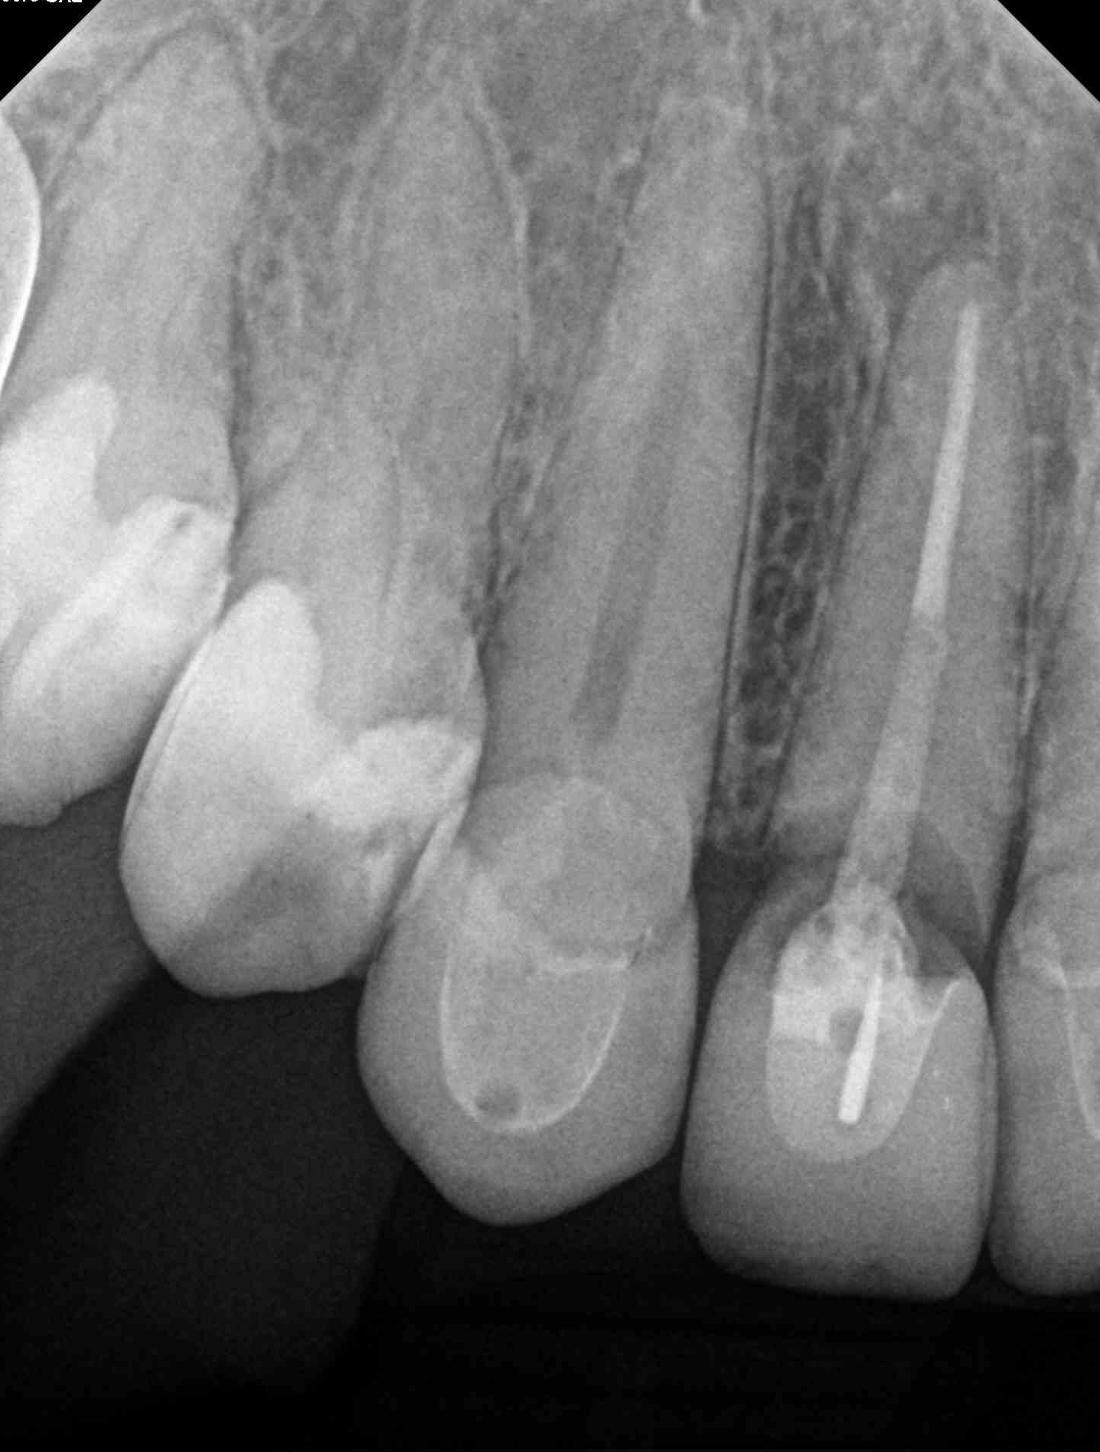

This young lady developed decay and a loose post under a crown. Unfortunately, the tooth could not be repaired and was removed. After a period of healing, a dental implant was placed by Dr. Brad Jordan. The final porcelain crown matches the crowns on her other front teeth very well.